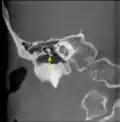

CT image of malleus -